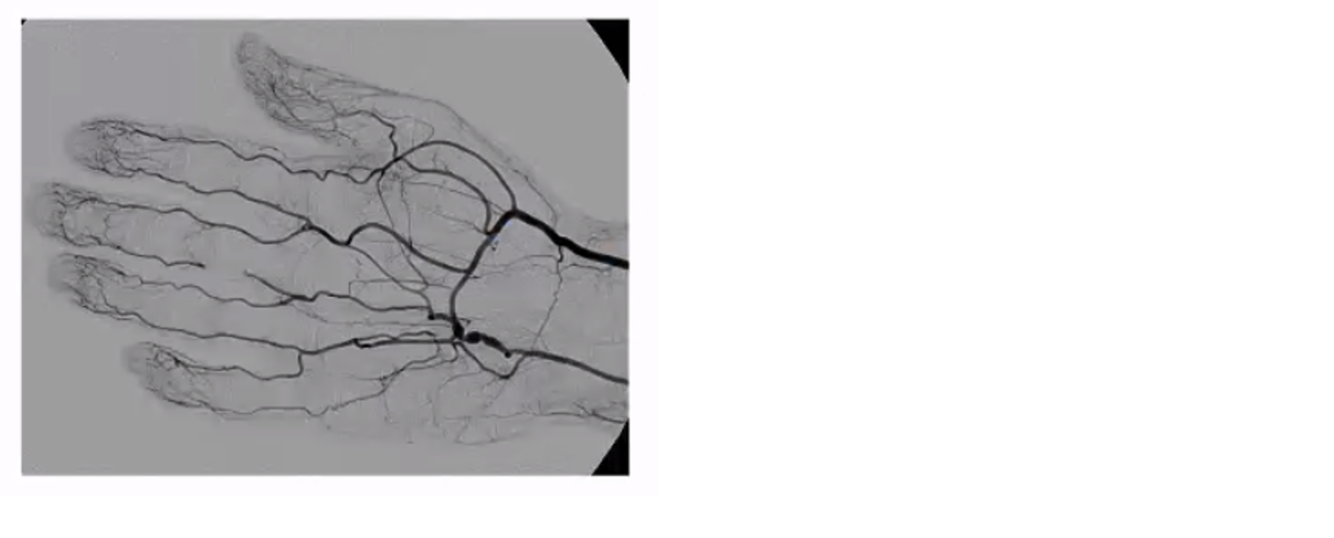

hypothenar hammer syndrome with distal embolus

vasospasm